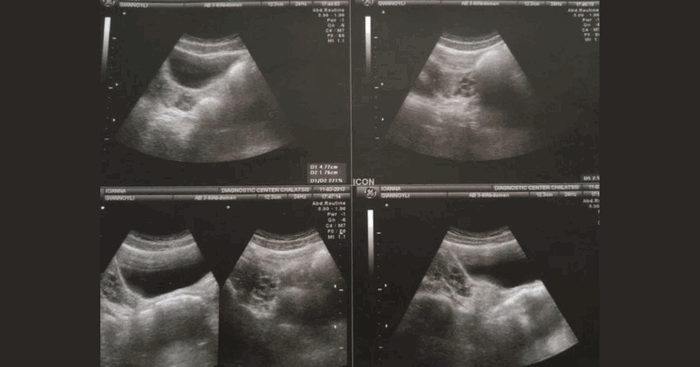

Because Joanna wasn’t born with a functional vagina, the doctors had to surgically make one for her.

Singapore gynaecologist suspended

Image source: iStock

“I stayed in a hospital for about two weeks,” she said. “Then I had to be about three months laying on a bed—I couldn’t get up. I did vaginal exercises in order to expand my new vaginal tunnel.”